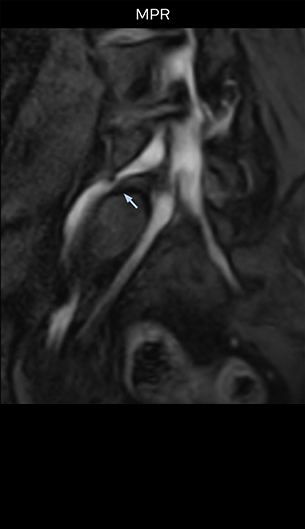

“Recently, the two surgical methods extreme and oblique lateral interbody fusion (XLIF and OLIF) have become mainstream for minimally invasive treatment of lumbar spinal canal stenosis and intervertebral foramen stenosis. With these surgical techniques, the spine is approached from the flank, and prior knowledge of the exact anatomy of the lumbosacral plexus would be extremely helpful. To that end, high slice resolution (less than 1 mm acquisition) that enables sharper sagittal MPR images will be needed.”

“For both brachial and lumbar plexus, we are currently using a 230 mm FOV and voxels of about 1 x 1 x 2 mm acquired (1 x 1 x 1 mm reconstructed). This provides us a good representation of the nerves, even though this FOV is relatively small. Regarding the inplane resolution, we hope to be able to bring that down to 0.7 mm, similar to our typical 2D multislice T2W images,” says Tanji.